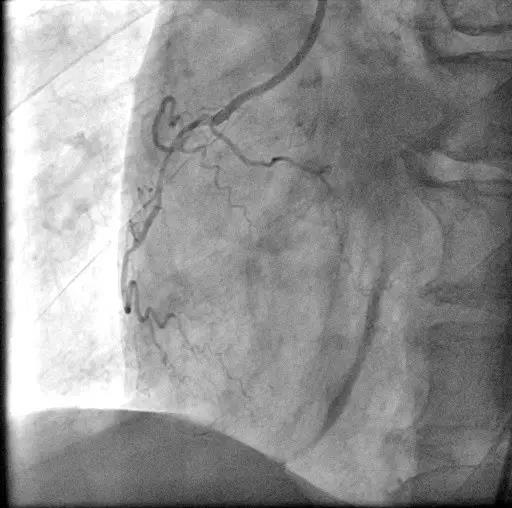

左旋支闭塞